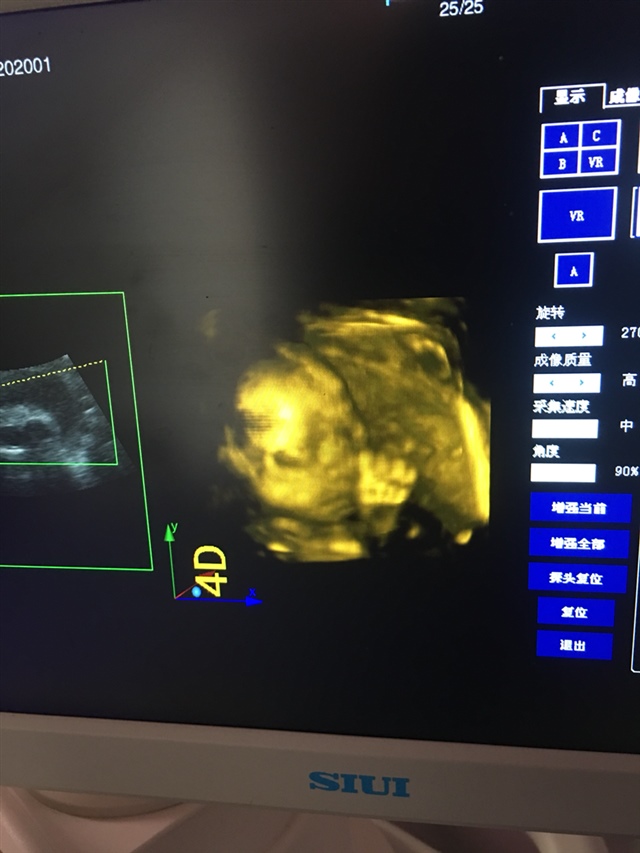

孕33周+2天